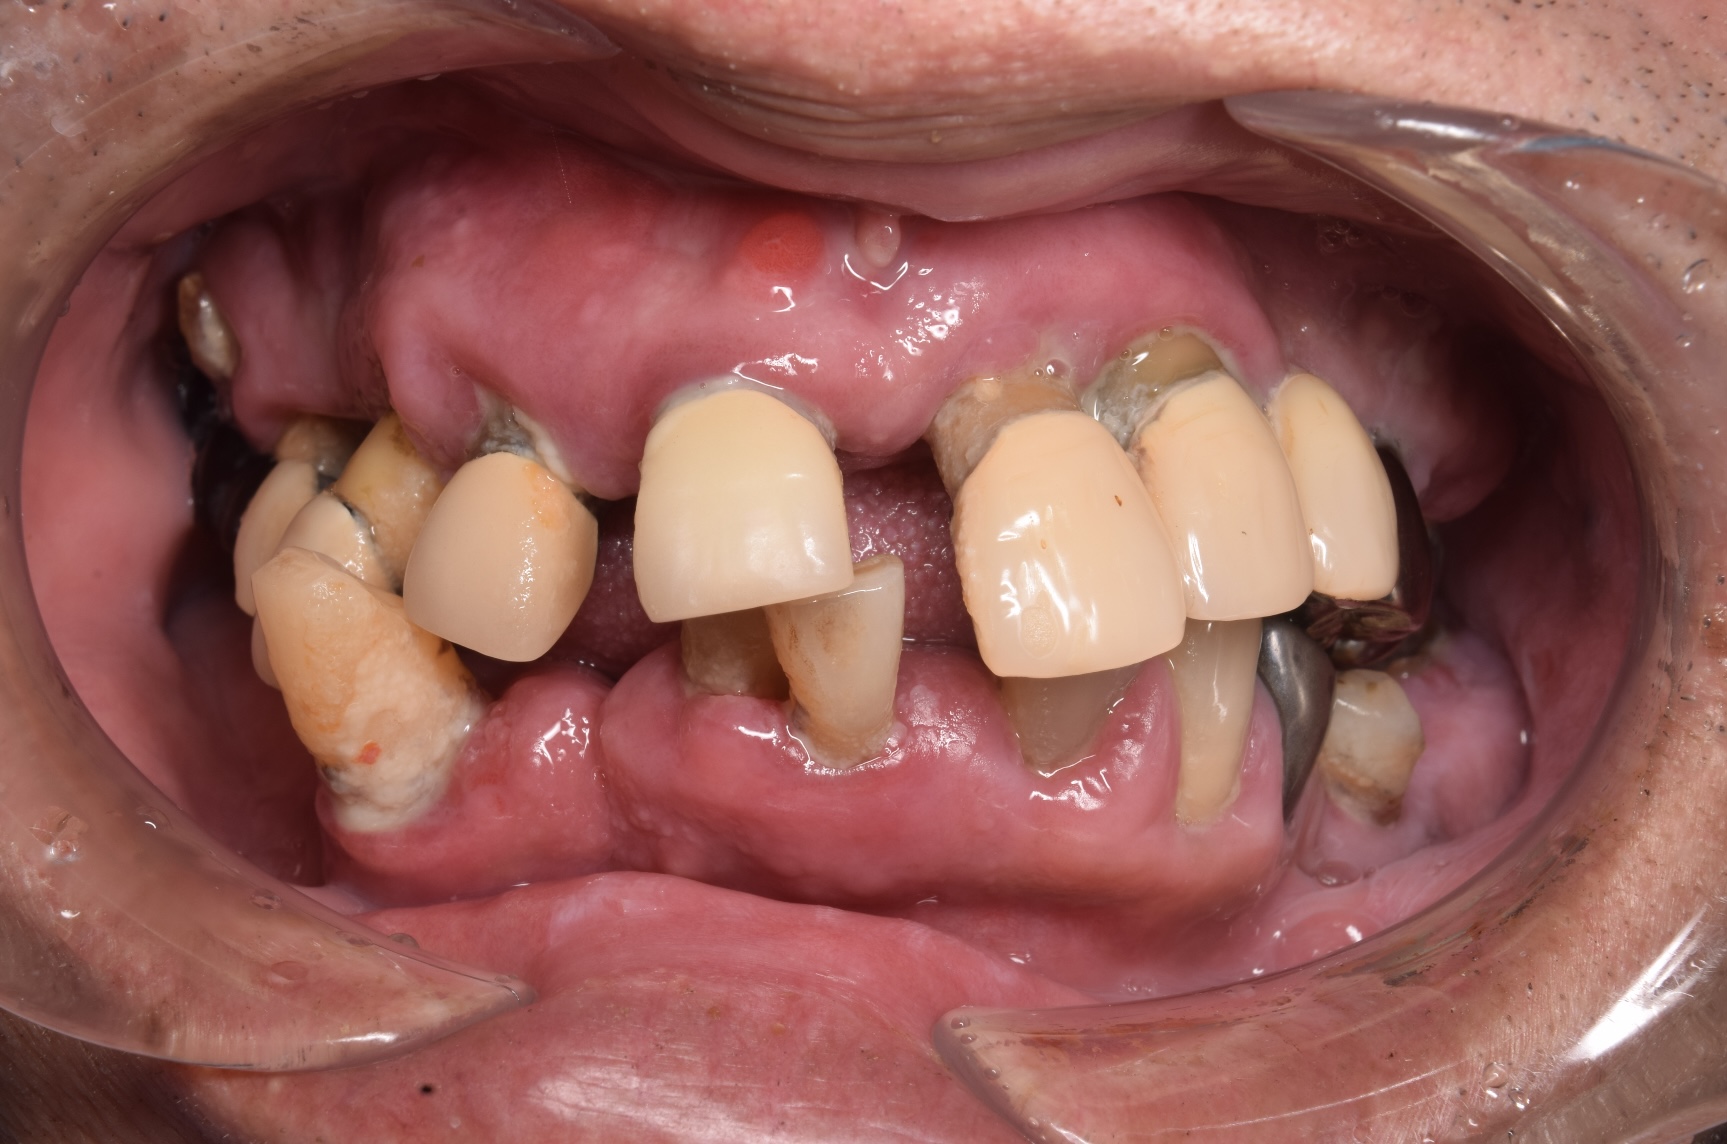

CASE

1